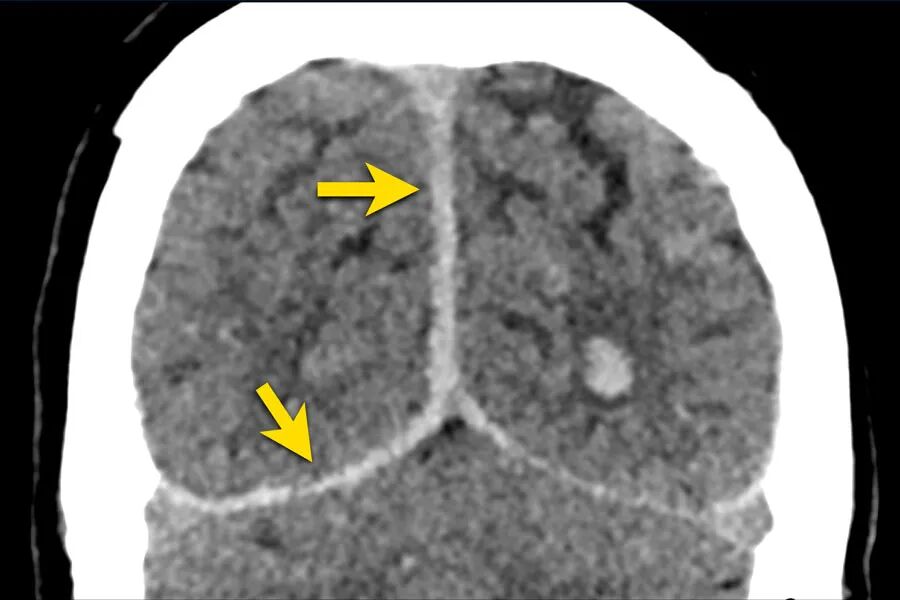

等密度硬膜下血肿

血肿的密度会降低,可能与脑的密度相同,从而使血肿的检测变得困难。

下图一例硬膜下血肿,很难发现(箭头)。

注意,在较高的水平上有双侧硬膜下血肿。

在罕见的情况下,急性硬膜下血肿可能与大脑等密度。

这种情况见于严重贫血、弥散性血管内凝血,或血肿被脑脊液稀释。

当一个慢性硬膜下血肿(>21天)变成低密度,可以和与脑脊液等密度,它可能模拟一个积液。

硬膜下血肿可沿大脑镰和小脑幕扩散,如本例所见。